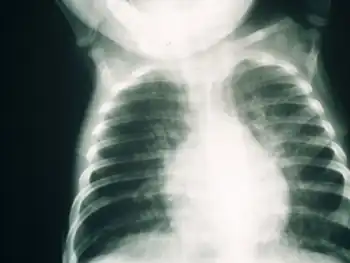

SCID patients are usually affected by severe bacterial, viral, or fungal infections early in life and often present with interstitial lung disease, chronic diarrhea, and failure to thrive.[3] Ear infections, recurrent Pneumocystis jirovecii (previously carinii) pneumonia, and profuse oral candidiasis commonly occur. These babies, if untreated, usually die within one year due to severe, recurrent infections unless they have undergone successful hematopoietic stem cell transplantation or gene therapy in clinical trials.[6]